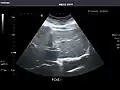

Liver: Diffusely homogeneous and normal in echogenicity. No focal mass or contour nodularity. No intrahepatic biliary ductal dilatation.

Portal Vein: Patent main portal vein.

Gallbladder: No stones, wall thickening, or pericholecystic fluid.

Common Bile Duct: Nondilated measuring 1.3 mm at the level of the porta hepatis.

Pancreas: Visualized portions unremarkable.

Spleen: Normal in size.

Kidneys: Right and left kidneys measure 11.5 cm and 12 cm in length respectively. No hydronephrosis. Small left lower pole kidney cyst.

Ascites: None.

Aorta: Visualized portions normal in caliber, 16 x 15 mm.

IVC: Normal.

IMPRESSION:

Normal abdominal ultrasound.